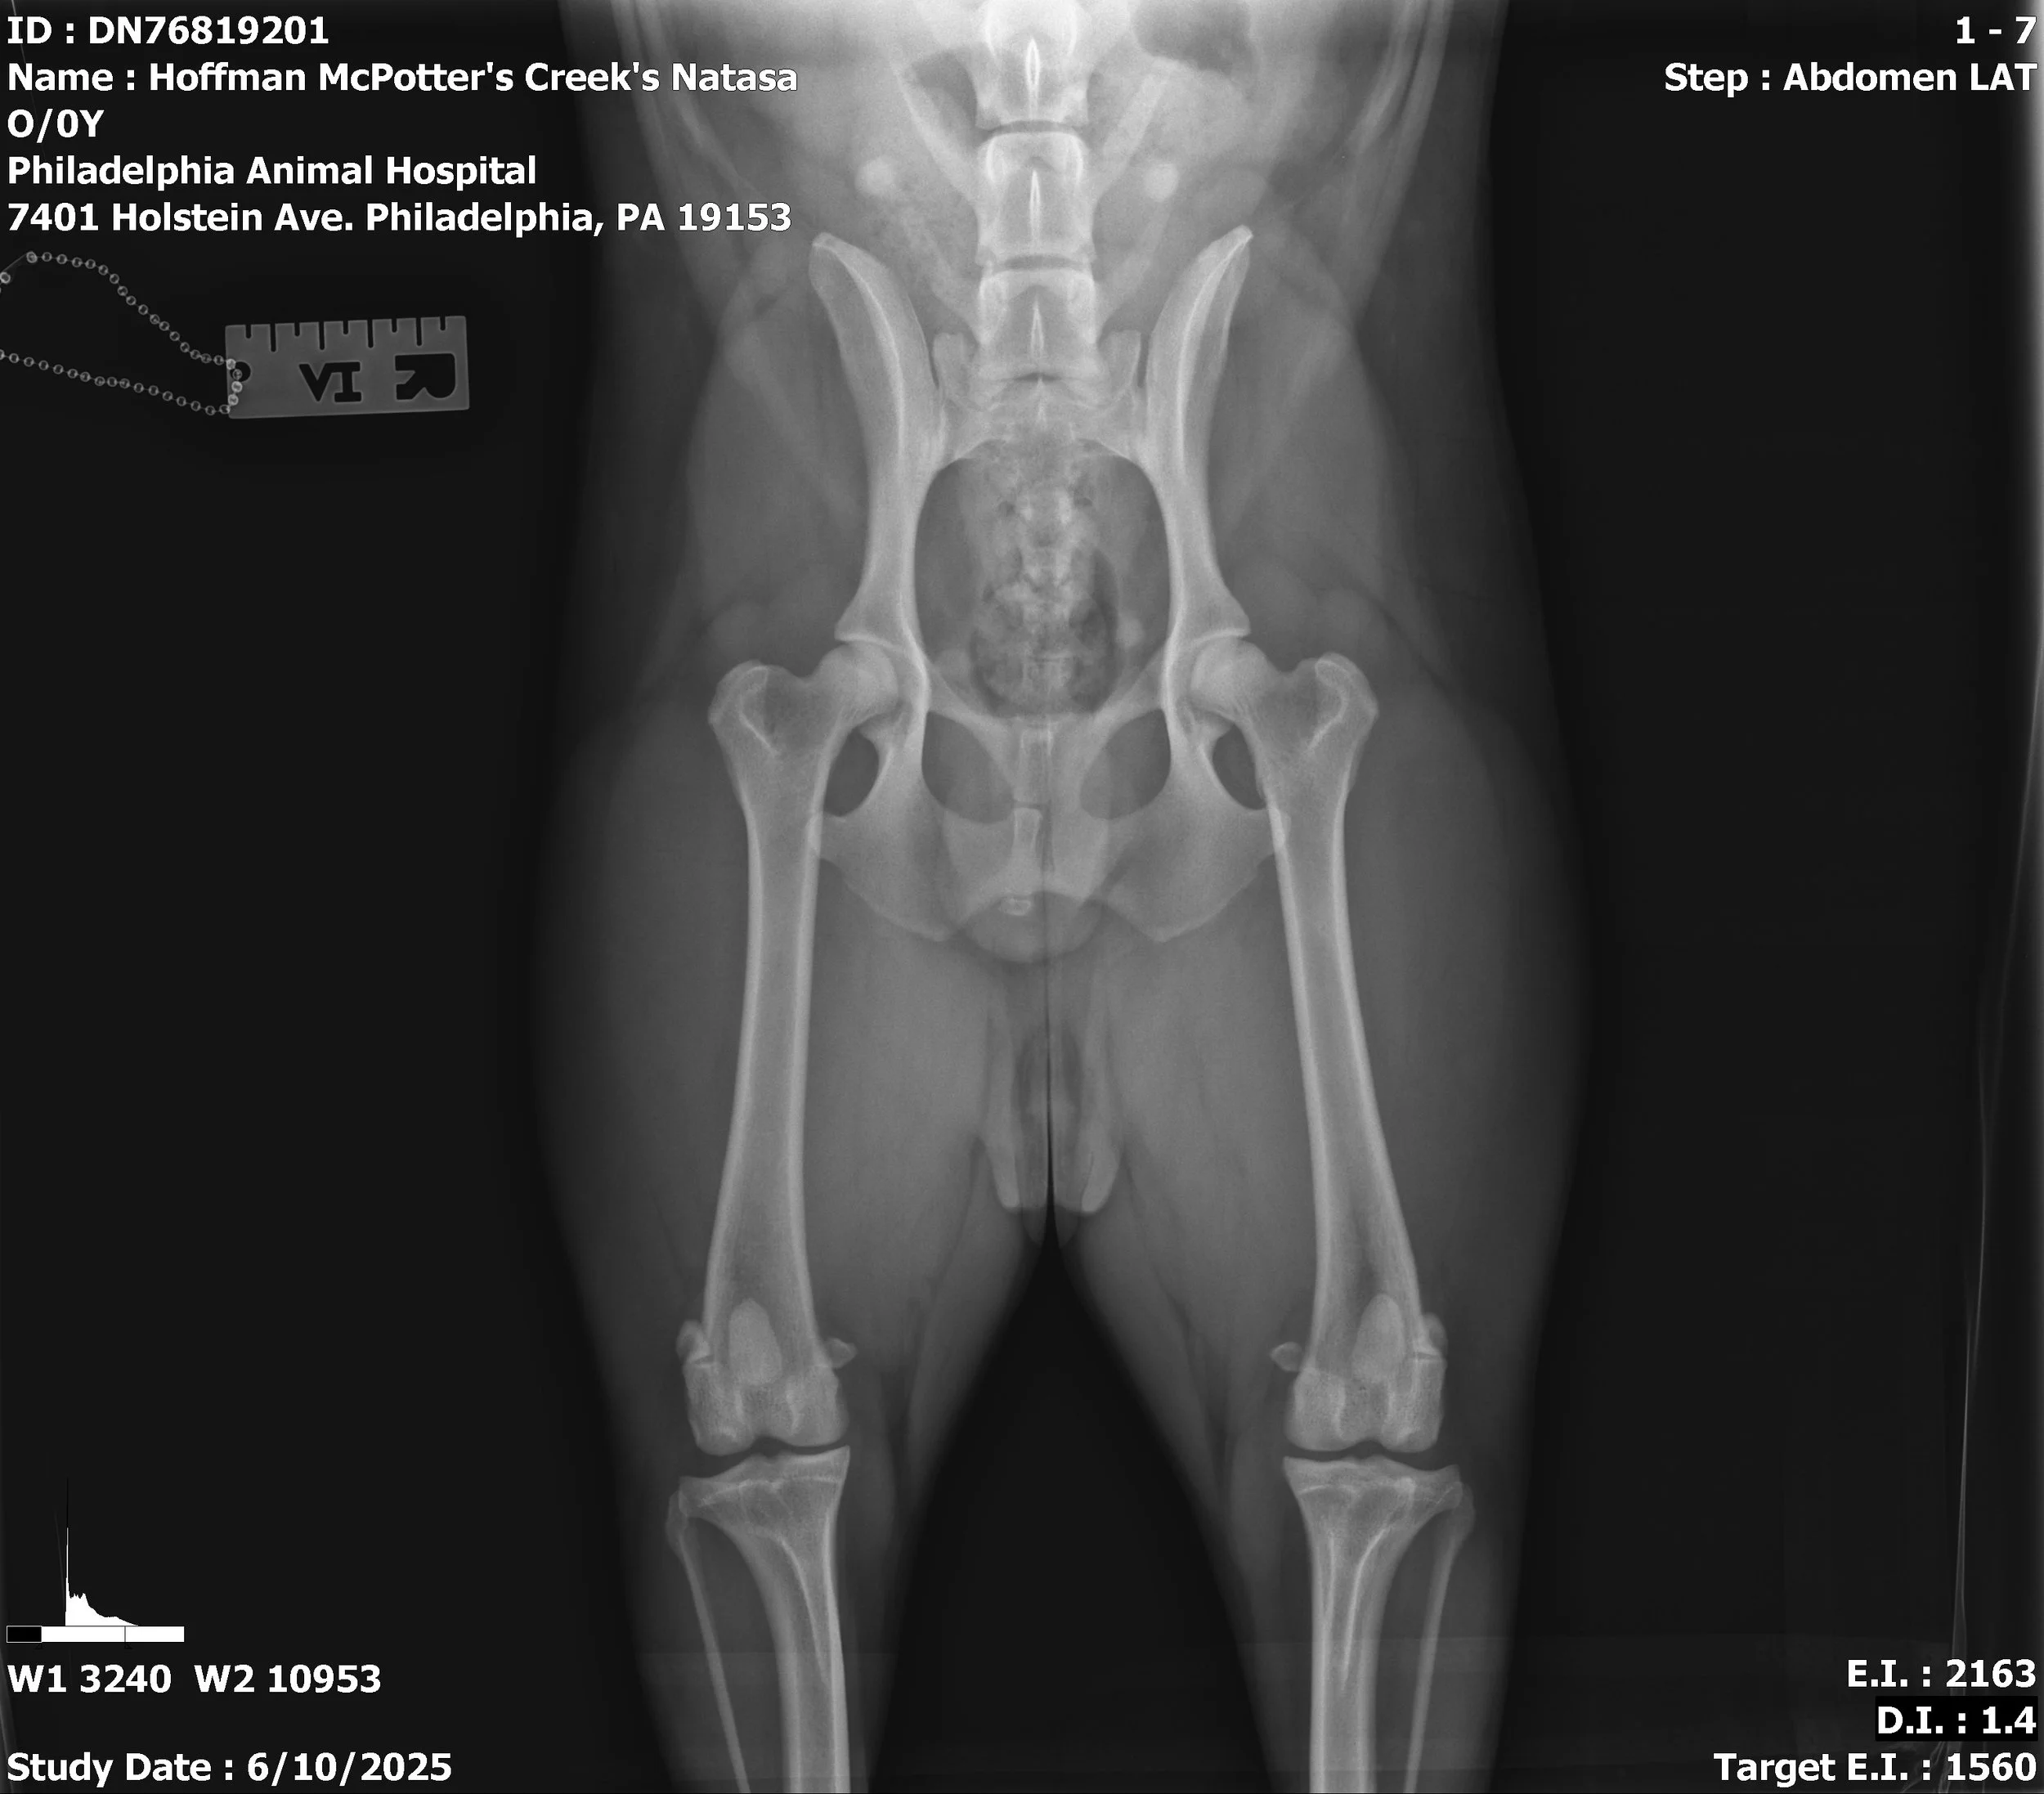

GCH CH McPotter's Creek's Natasa FDC DCAT DS DJ AJ TKN “Iris”

CHIC#: 210211

Iris is our foundation bitch who we imported in 2023 with her brother Coro. She has been nothing short of a good time since then! This girl has the perfect blend of drive and temperament that we like to strive for in all of our mudis. She completed her CH at 9 months old, her GCH at 18 months and her Dock Senior at only 14 months. The sky is the limit with this girl!